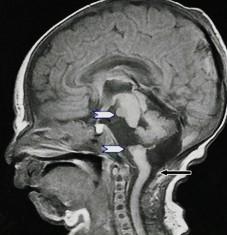

White arrows: Small pons remnant with nonformation of the midportion of the brainstem

Clinical: cranial neuropathies

Associated with small cerebellum

Abnormal vertebrobasilar vasculature

Etiology?

very early vascular insult?

No gliosis to suggest hypoxia or ischemia

In animals: seen with hox gene deletions leading to lack of single rhombomere development, so brainstem “short” but typically not fully disconnected